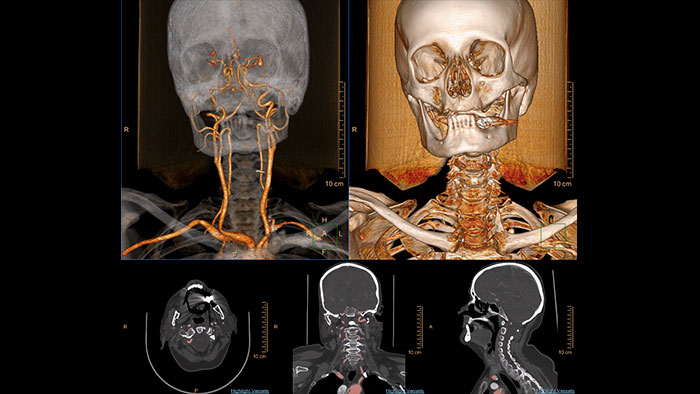

Advanced Vessel Analysis (AVA)

Multi Modality Advanced Vessel Analysis (AVA)

Comprehensive vascular analysis planning

Designed to examine and quantify different types of vascular lesions from CTA and MRA scans. It accommodates different modes of inspection, allows labeling different vascular lesions, and helps navigating through multiple findings.

Demonstrated to reduce the post-processing time by 50% when compared to manual Head & Neck CT angiography (CTA) analysis*.

Benefits

• Ability to choose which Head & Neck Bone Removal method to be used (Standard vs. Smooth).

• Customizable Volume rendering “smoothness” for the 3D Head & Neck vascular structure using a smoothness control.

* Ardley N et al. Efficacy of a new post processing workflow for CTA head and neck. ECR 2013 / C-1760.